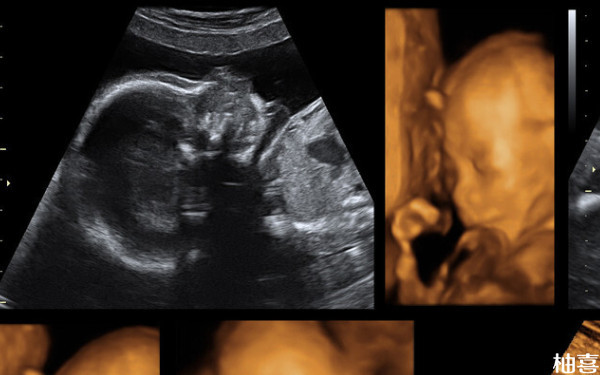

39周B超看男女还会翻盘吗?

39周B超看男女还是有可能会翻盘的,毕竟宝宝可能会存在遮挡的情况,导致判断不是很准确,只是有一点要注意,目前国内禁止非医学进行性别筛查和判断的,因此孕妇在医院产检时,医生并不会告知宝宝的具体情况,而网上的判断方法,并不能达到百分之百的准确率,因此还是有一定翻盘几率的。